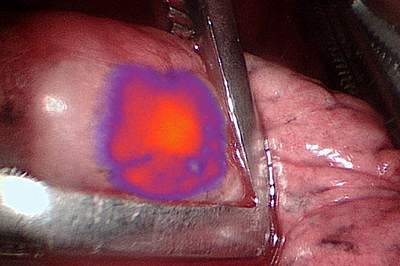

Some imaging tests use contrast agents to make the tumor more obvious against healthy tissue. A new contrast agent called OTL38 consists of folate, a B vitamin, labeled with a dye. Receptors for folate are found on most cells, but many types of cancer cells have unusually large numbers of folate receptors on their surfaces. After a patient receives an intravenous (IV) injection of OTL38, the contrast agent flows throughout the body and binds to folate receptors. When exposed to light of a certain wavelength, tissues with high levels of OTL38-labelled receptors glow with fluorescent light.

All patients received the OTL38 contrast agent several hours before surgery. During surgery, OTL38 caused 60 of the 66 previously detected nodules to glow. OTL38 also enabled the detection of 9 additional nodules not found by PET.

The surgeons removed all 75 nodules and sent them to the pathology lab. Tests confirmed that 68 nodules were cancer. The PET scan had shown 50 of these 68 cancers as suspicious for cancer; OTL38 had shown 65 of the 68 cancers as suspicious for cancer.

OTL38 also helped identify tumors that the surgeons could not see with regular white light or feel during surgery. Of the 17 nodules measuring less than 1 cm, 15 were detected with OTL38 and verified to be cancer. The other two nodules were benign and not detected by OTL38. PET detected four of these 15 small cancers. With PET, one nodule it detected turned out to be benign.